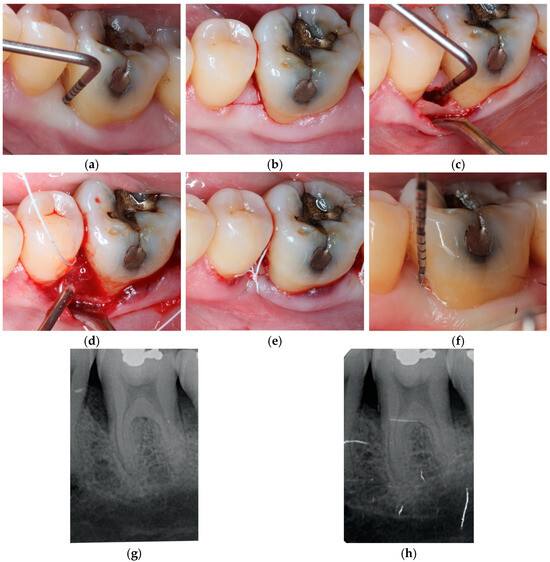

2. Materials and Methods

2.1. Design of This Study

3.2. Clinical and Radiographic Results